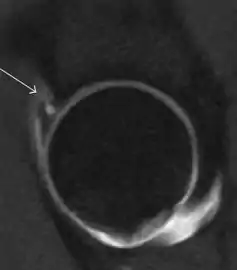

Most of the angles and measurements described in the plain radiograph section can be accurately reproduced on MRI. In addition, the superiority of MRI resolution with intra-articular contrast allows detection of labral and chondral abnormalities that may influence the choice of medical, percutaneous, or surgical management (Figure 9).[1]

Figure 9:

Sagittal T1 weighted image showing anterosuperior labral tear.[1]

Sagittal T1 weighted image showing chondral lesion.[1]

MR arthrography has proven superior in accuracy when compared to native MR imaging. It is considered the best technique to assess the labrum. Knowledge of the normal variable morphology of the labrum helps to differentiate tears from normal variants. A triangular shape is most commonly seen in 66% of asymptomatic volunteers, but round, flattened, and absent labra can also be found in asymptomatic populations. MR arthrography has demonstrated sensitivity over 90% and specificity close to 100% in detecting labral tears. Loose bodies are demonstrated as filling defects surrounded by the hyperintense gadolinium.[1]

Association between labral tears and chondral damage has been demonstrated. This underscores the interaction between cartilage and labrum damage in the progression of osteoarthritis. Chondral damage to the posteroinferior part of the acetabulum as a contrecoup lesion occurs in approximately one-third of pincer cases secondary to persistent abutment on the anterior part of the joint leading to a slight posteroinferior subluxation. This is considered a bad prognosis sign.[1]